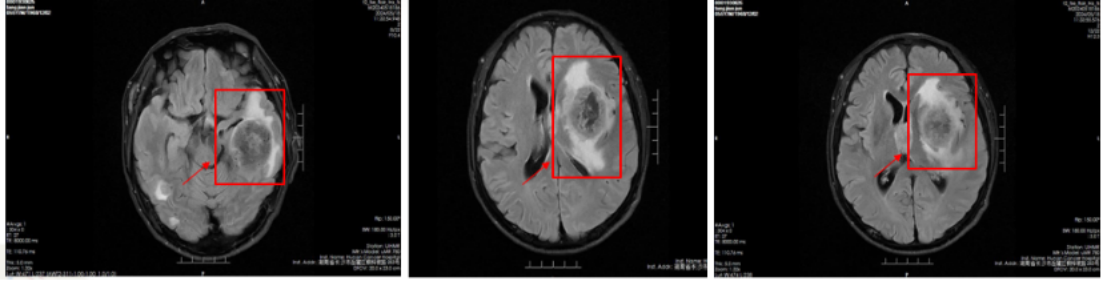

治疗前头部(2024-5-14):脑内多发结节肿块,考虑转移瘤可能性大(图3)。

图3

治疗后头部(2024-7-17):脑内多发转移瘤较前明显缩小,减少,活性降低(图4)。

图4